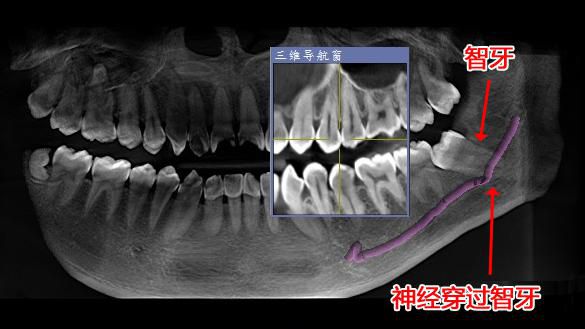

△經西諾德3D口腔全景CT檢查發現神經穿過智牙。

爲預防神經損傷,拔除智牙前,有必要先通過口腔全景CT了解牙根與下颌神經管的關系。如盲目操作易損傷神經,出現下唇及颏部皮膚不完全性麻木或兼有燒灼、刺痛、蟻走等異常感。